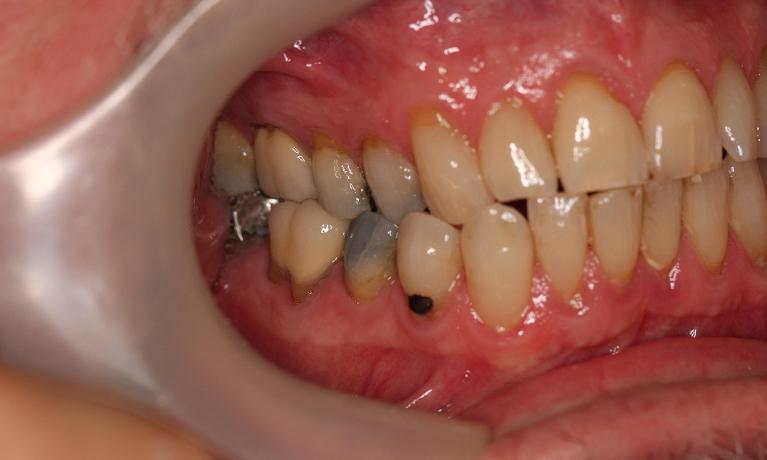

This man in his 50s was unhappy with the amalgam filling used to fix cavities. After discussing options, we agreed to fix his appearance by putting crowns on the teeth which create more of a natural look. This patient was very happy with the end result and is now in maintenance mode.